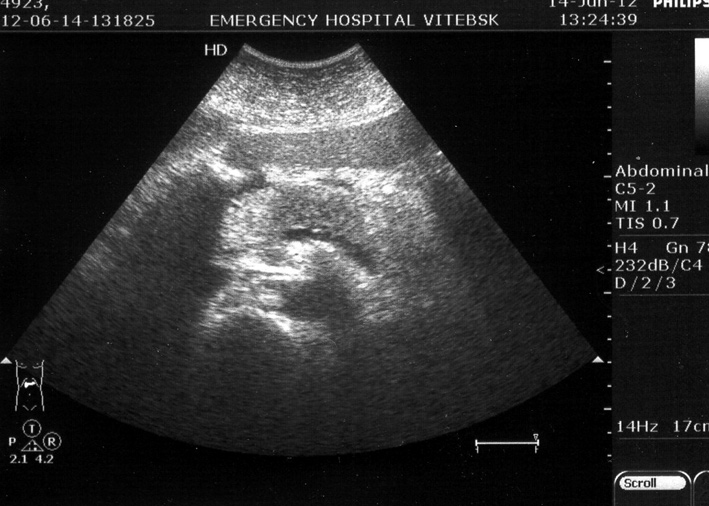

Осмотр на следующий день

Philips InVisor

На сонограммах о.панкреатит, в первый и следующий день после начала заболевания. Обратите внимание на изменение эхогенности железы и на два признака, которые позволили диагностировать заболевание в первый же день.

Самое интересное что эхогенность железы нормальная, даже несколько повышена, а вот размеры и парапанкреатический инфильтрат за о.панкреатит.

Да, видим выпот кпереди от панкреас (действительно, в сальниковой сумке) и выпот между телом панкреас и селезеночной веной.

Причем второй признак - по моим наблюдениям - является самым ранним и быстро исчезает.